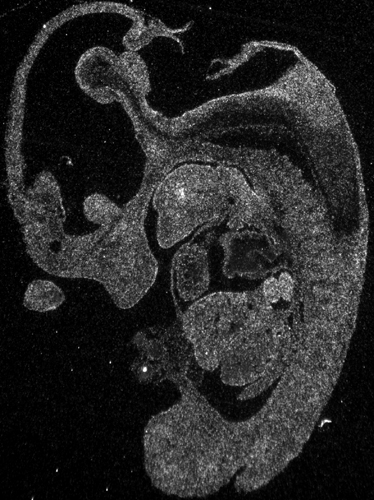

Specimen

g03047 E11.5:

embryonic day 11.5

Genetic Background:

C57BL/6

Age:

Sex:

Not Specified

Type:

section

Fixation:

4% Paraformaldehyde

Embedding:

Cryosection